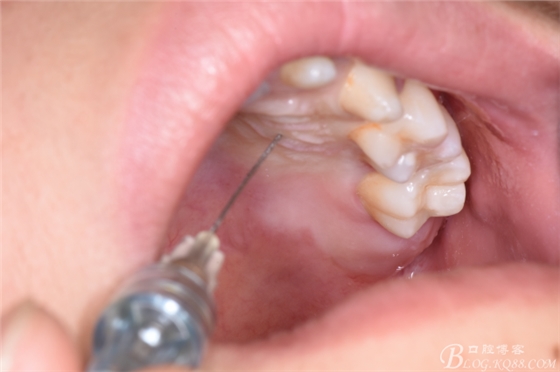

圖4.唇側(cè)、腭側(cè)局部無(wú)痛浸潤(rùn)麻醉